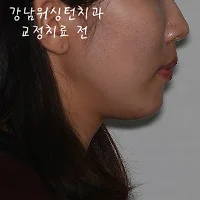

이번에는 돌출입교정전후 옆모습 변화사진을 보시도록 할게요.

워싱턴치과 돌출입교정전후 사진입니다.

돌출입교정전에는 치아의 돌출로 인해 입을 쭉 내밀고 있는 모습이 보이지만!

강남워싱턴치과에서 돌출입교정 후에는 돌출된 치아가 안으로 들어가면서 입을 내밀고 있는듯한

모습이 많이 개선이 되셨어요^.^*

이로인해, 코가 높아보이는 효과까지 드네요.

신기한 돌출입교정전후 -